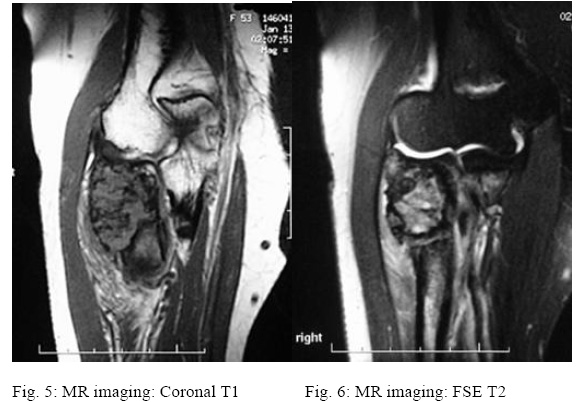

CHONDROSARCOMA, PROXIMAL RADIUS (Fig.1:-6:) History: 33 y/o male with pain and swelling about elbow. Findings: Plain films show an expansile lesion. The MR shows cortical destruction and soft tissue extension. Diagnosis: Chondrosarcoma, proximal radius.

Magnetic Resonance Imaging (MRI) can be helpful in differentiating between benign and malignant lesions

in several ways. First, the degree to which the tumor fills the medullary canal can be helpful (Figure 4).

Greater than 90% medullary involvement can be suggestive of chondrosarcoma, while the absence of 90%

medullary involvement of non-contiguous areas of cartilage within the bone can suggest the presence of an

enchondroma (Colyer et al., 1993). In addition, the timing and progression of gadolinium contrast

enhancement patterns may help direct a clinician toward or away from a diagnosis of malignancy (Geirnaerdt

et al., 2000). Early enhancement (within 10 seconds of arterial enhancement) may be seen in

chondrosarcoma but not in enchondroma. Many surgeons consider MRI critical for surgical planning because

it can illustrate the extent of tumor involvement in bone and soft tissues.